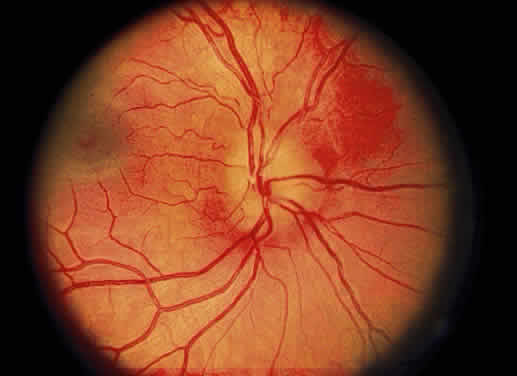

Consider the variation in pigmentation and choroidal blood flow. In one extreme, the albino, the fundus has a bright orange color because the pigment epithelium contributes little to fundus color in this condition. At the opposite extreme is the patient with congenital melanosis oculi such as seen with nevus of Ota. In this condition, the density of normal choroidal melanocytes masks much of the orange color of the choroid and changes the general fundus color to a gray-orange. If the choroid and pigment epithelium were absent focally, the observer would be looking through transparent retinal tissue at the sclera, which is white. This is the basis for the ophthalmoscopic appearance of a coloboma (Fig. 1). With the exception of the macula, in which xanthophyll pigment may impart a yellow color, the normal neurosensory retina is transparent. Despite this transparency, when the retina is focally absent, the orange color of the underlying choroid is enhanced. This color contrast may aid the ophthalmoscopic detection of retinal breaks (Fig. 2). Nevertheless, remember that the normal retina does not contribute color to the fundus. In fact, a loss of retinal transparency or the acquisition of color by neurosensory retinal tissue is indicative of a pathologic change.

Fig. 2. Fundus photograph of a retinal tear. The pigment epithelium and choroid visible through the retinal break have an orange-red color. The retina surrounding the tear has lost its transparency because of edema and underlying fluid.